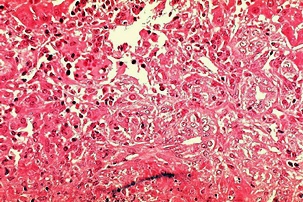

황달이 생기는 이유는 담즙색소라고 알려진 빌리루빈이 과도하게 생기기 때문입니다. 빌리루빈은 우리 몸의 오래된 적혈구가 파괴되면서 생기는 물질인데요. 이 물질은 담즙에 녹아서 우리 몸의 배설물과 함께 배출이 되는 것이 정상적이지만 빌리루빈의 과잉생산이나, 간의 장애, 간세포나 담도의 손상에 의해 빌리루빈이 역류할 경우 발생된다고 합니다.

황달의 증상

황달이 생겼을 때 나타나는 대표적인 증상은 소변의 색깔이 진하게 변하는 것입니다. 이는 과도하게 분비된 빌리루빈이 소변으로 배출되기 때문인데요. 이러한 경우 소변의 색이 진한 갈색으로 변하게 됩니다. 또한 피부에 담즙색소가 침착되면 눈이 노랗게 변하는데요. 눈에 노랗게 된다고 모두 황달 증상을 의심할 수 있는 것은 아닙니다.

보통 눈과 피부, 소변의 색깔에 모두 이상이 생긴 경우 황달 증상으로 볼 수 있으며 병원에 내원하여 진단을 받아보는 것이 권장됩니다. 황달이 생기는 경우 피부 가려움증을 동반한다고 하는데요. 이러한 이유는 배출되어야 할 화학물질이 피부의 신경조직을 자극하여 발생한다고 추측하고 있습니다.